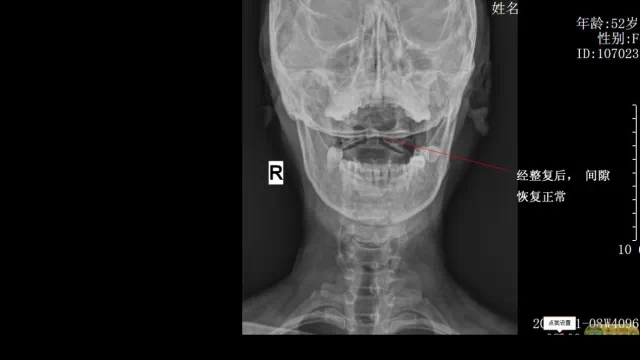

崔阿姨,湖北襄阳人,反复颈背部疼痛、打嗝8年,经多方治疗效果不佳,拍片显示寰枢椎关节失稳,我们对其采用进口的整脊枪结合脊椎的生物力学原理进行整复后,崔阿姨的颈背部疼痛等症状消失,打嗝明显减少。

整脊后复查